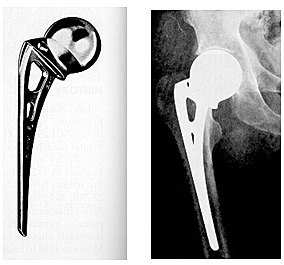

Después de evidenciar el desgaste del implante de los judet,El siguiente adelanto en el desarrollo de la artroplastia de cadera consistió en el diseño de endoprótesis metálicas con vástagos medulares para la fijación esquelética. Los dos modelos más populares fueron desarrollados en Estados Unidos por Fred Thompson en 1950 y A.T. Moore en 1952.

• VÁSTAGOS MAS LARGOS....

VÁSTAGOS MAS LARGOS....

permitían la transmisión de las fuerzas de soporte de peso a lo largo del eje del fémur, en lugar de generar fuerzas de presión a nivel del cuello femoral como ocurría en la prótesis acrílica de los hermanos Judet. Estos dispositivos que se basaban en la fijación a presión dentro del canal medular. La prótesis de Moore presentaba una fenestración en la parte superior del vástago femoral para permitir el crecimiento óseo en su interior aumentando así su fijación ósea.